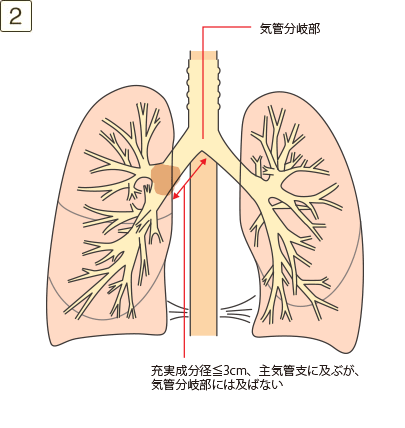

充実成分径>3cmでかつ≦5cm、または充実成分径≦3cmでも以下のいずれかであるもの

- ・主気管支に及ぶが気管分岐部には及ばない